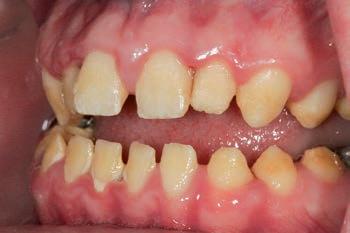

Clinical case

The patient was an 18-year-old male with a confirmed family history of Xlinked AI, who was otherwise in good health and non-smoking. Upon initial clinical presentation, a low-caries-risk, complete adult dentition from second molar to second molar was present, which was globally affected by pitted, hypoplastic and hypomineralised AI, dento-alveolar disproportion and an unusual generalised open occlusion, characterised by one occlusal contact at the right first molar region in the maximum intercuspation position (MIP). Historical paediatric management of the dentition involved placement of stainless steel crowns at the first permanent molar sites to protect the emerging dentition from post-eruptive breakdown and loss of occlusovertical dimension during the mixed dentition phase.6 On adult presentation, all but the UR6 stainless steel crown remained intact. Oral hygiene was poor, with evidence of plaque-induced chronic gingivitis (Figure 1). The patient reported experiencing severe, widespread hypersensitivity upon hot, cold, osmotic and masticatory stimuli, and feeling aesthetically self-conscious. The patient was seeking comprehensive fixed prosthodontic care and was well informed about the nature of such treatment, having witnessed his elder siblings undergo similar treatment.

1: The patient’s initial situation on clinical presentation to the tertiary care referral centre. The dentition is globally af fected by amelogenesis imperfecta, associated with dentoalveolar disproportion and an unusual presentation of open occlusion.